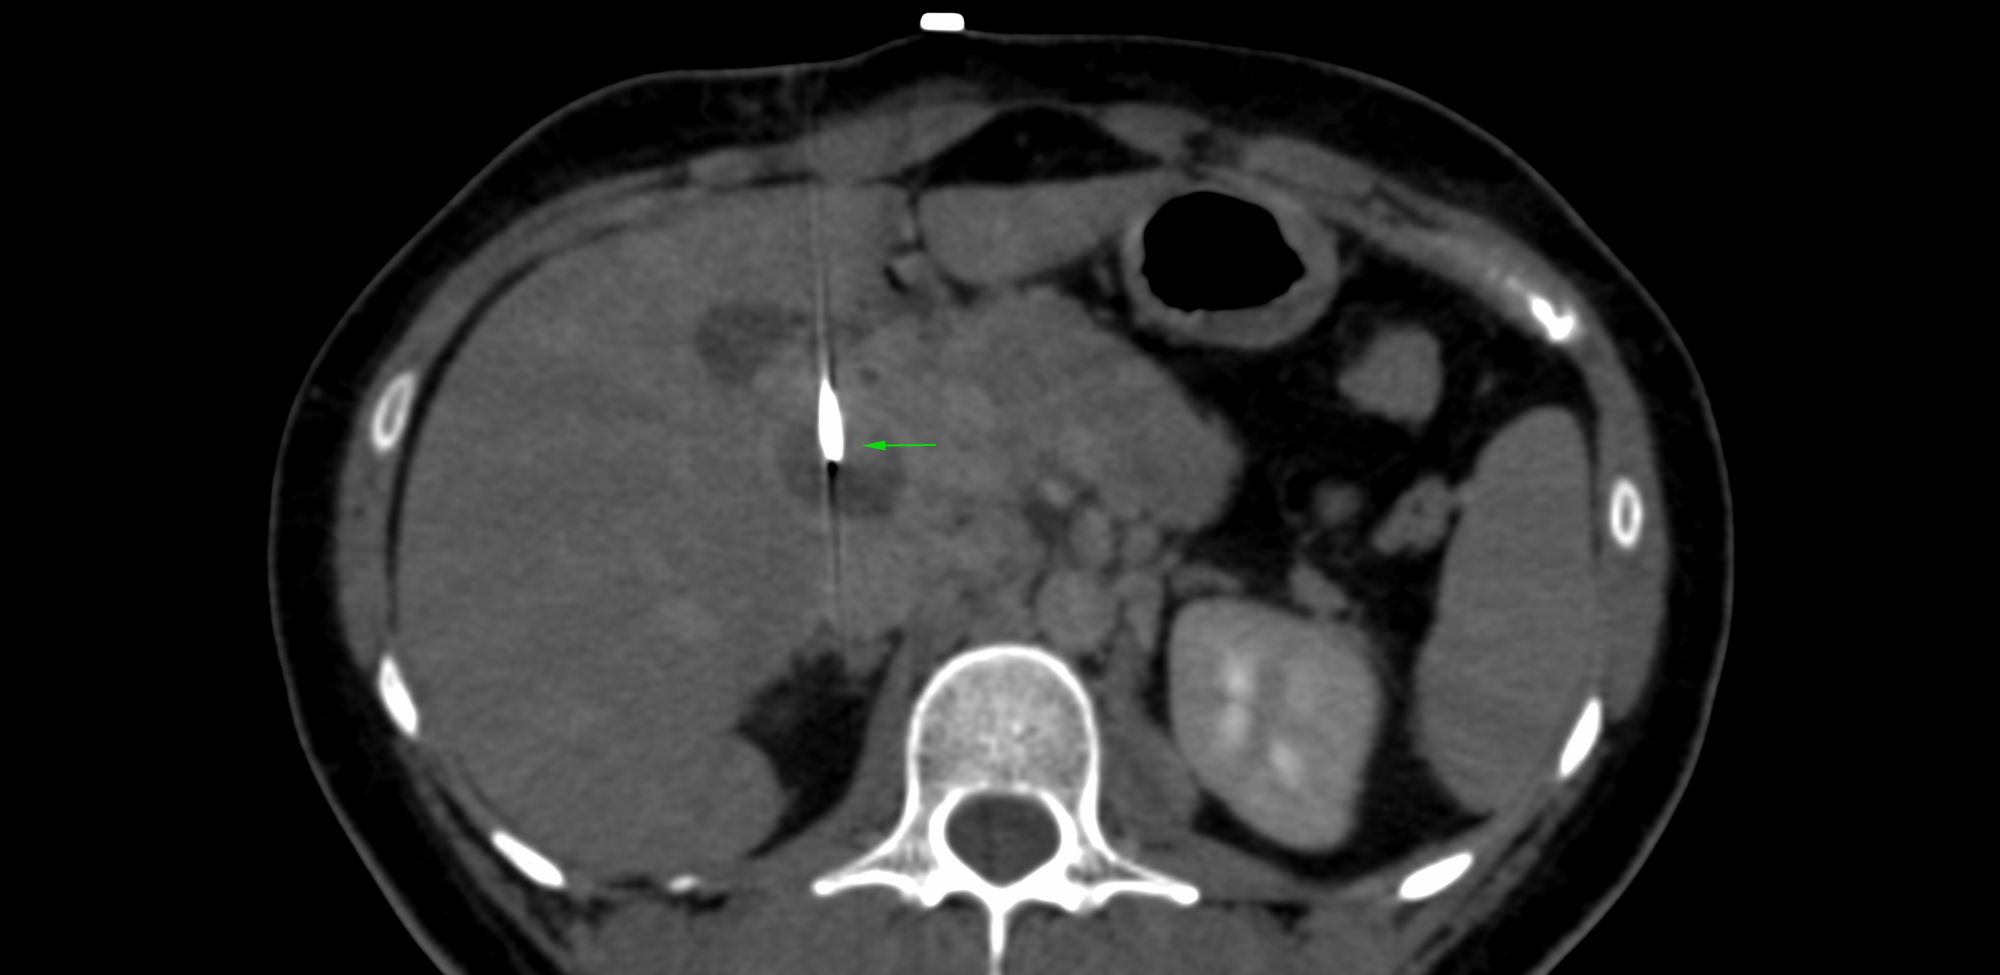

Case 6: Mass in the Uncinate Process of Pancreas

Bhavin Jankharia - 23 February 2021